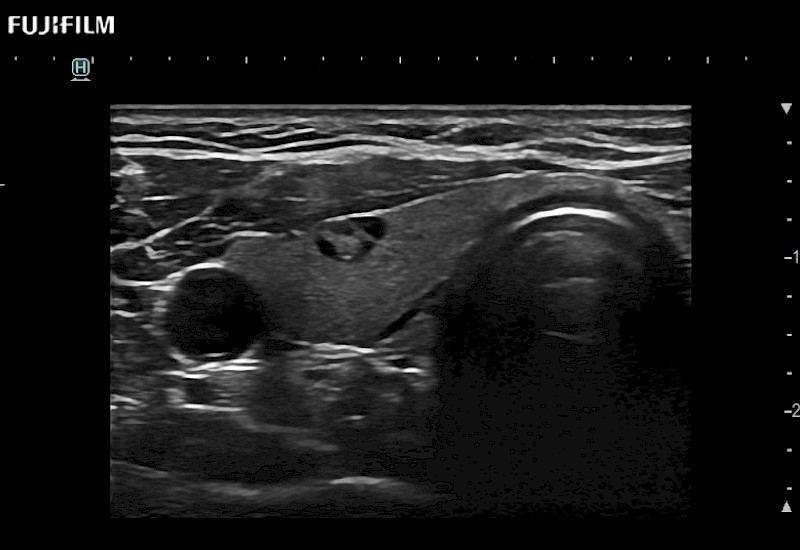

Fujifilm Healthcare understands that Surgical Oncologists demand excellence in their operating rooms — from their staff and the equipment they depend on. Fujifilm Healthcare's dedication to Surgical Oncologists provides outstanding ultrasound technology, professional support and the specialized tools necessary to best perform comprehensive real-time ultrasound imaging.

For precise surgical oncology ultrasound imaging, Fujifilm Healthcare offers premium level solutions that include:

for use during open and laparoscopic procedures: Tumor localization & staging, Ablation, Resection, Biopsy, Transplant, Abdominal exploration, Robotic surgery

Our dedication to Surgical Oncology allows us to offer superior image quality, outstanding system reliability and intuitive use of cutting edge technology.